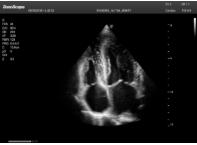

2相控陣探頭

探頭面是平面,接觸面小,近場(chǎng)視野最小,遠(yuǎn)場(chǎng)視野大,成像視野呈扇形,適用于心臟。

心臟探頭通常按應(yīng)用人群劃分為成人、兒童、新生兒三類(lèi):(1)成人心臟位置最深、搏動(dòng)速度慢;(2)新生兒心臟位置較淺、搏動(dòng)速度最快;(3)兒童心臟的情況介于新生兒與成人之間。

肥厚性心肌病-心尖四腔